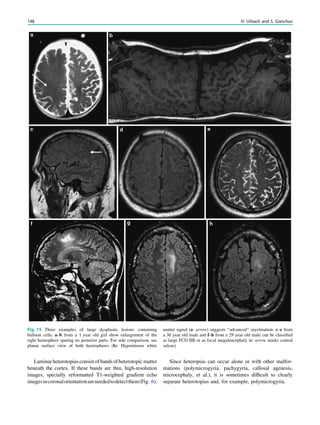

The Wada Test HorstUrbach and Jo¨rg Wellmer Contents 1 Introduction.......................................................................... 51 2 Angiographic Work-Up ...................................................... 52 2.1 IAP ......................................................................................... 52 2.2 Selective Wada Test.............................................................. 52 3 Complications Related to the Wada-Test......................... 53 4 Neuropsychological Work-Up ............................................ 53 5 Drugs ..................................................................................... 55 5.1 Amobarbital ........................................................................... 55 5.2 Methohexital .......................................................................... 55 5.3 Etomidate............................................................................... 55 5.4 Propofol.................................................................................. 55 References...................................................................................... 55 Abstract The Wada test or intracarotid amobarbital procedure (IAP) consists of the short inactivation of one brain hemisphere due to the injection of amobarbital or another short-acting anesthetic into the supplying inter- nal carotid artery (ICA). During the subsequent inacti- vation period, neurological functions such as language and memory can be tested to assess the respective functional reserve capacity of the contralateral hemi- sphere. Less frequent indications for a Wada test are the assessment of motor function and the identification of secondary bilateral synchrony in EEG. With the advent of high-resolution structural MRI assuring the morpho- logical integrity of the contralateral temporal lobe or hemisphere and functional MRI (fMRI) the number of Wada tests within the presurgical work up of epilepsy patients has decreased. However, it is still method of choice in epilepsy patients with suspected atypical or bilateral language representations according to fMRI, in patients with lesions interfering with the BOLD effect (e.g., cavernomas), and in children or intellectually challenged patients, in which fMRI cannot be used. 1 Introduction The neurologist Juhn Wada (Wada 1949, translation in Wada 1997) reported the effects of unilateral intracarotid injections of amobarbital on language in an article published in Japanese in 1949. While at the Montreal Neurologic Institute in the 1950s, Wada introduced his technique in the presurgical evaluation of epilepsy patients to determine language later- alization before surgery (Wada and Rasmussen 1960). Within a few years, it became evident that this technique could also be used to assess memory capacity in patients who were candidates for temporal lobectomy or amygdalohippocamp- ectomy. In this pre-imaging era, further indications were the lateralization of the seizure focus and the prediction of H. Urbach (&) Department of Neuroradiology, University Hospital Freiburg, Germany e-mail: horst.urbach@uniklinik-freiburg.de J. Wellmer Ruhr-Epileptology, Department of Neurology, University Hospital Knappschaftskrankenhaus, Bochum, Germany H. Urbach (ed.), MRI in Epilepsy, Medical Radiology. Diagnostic Imaging, DOI: 10.1007/174_2012_619, Ó Springer-Verlag Berlin Heidelberg 2013 51

• 56.

postoperative outcome (Spenceret al. 2000; Lee et al. 2003; Baxendale et al. 2008, Baxendale 2009 ). For more selective memory testing and in order to avoid confounding effects of hemispheric language inactivation, selective Wada tests with amobarbital injections into the posterior cerebral artery (PCA), the anterior choroidal artery (AchoA) or the middle cerebral artery or its branches have been developed (Jack et al. 1988, 1989; Wieser et al. 1997; Urbach et al. 2001, 2002). However, as an invasive procedure with an inherent risk of permanent neurological deficits, Wada tests are per- formed on selected patients only occasionally (Haag et al. 2008; Wagner et al. 2012). 2 Angiographic Work-Up 2.1 IAP A 5F sheath is placed in the femoral artery ipsilateral to the intended intracarotid injection side. A 5F vertebral catheter is navigated into both common carotid arteries and digital subtraction angiograms are obtained before the catheter is advanced into the ICA on the injection side. The reason for bilateral anterior circulation angiograms is to rule out prominent anastomotic channels from the ICA to the verte- brobasilar system and to assess the angiographic supply to the hemispheres (Fig. 1). For example, if both anterior cerebral arteries are fed via one ICA, amobarbital injection in this ICA often leads to an ‘‘mutistic’’ patient for the test period. Before amobarbital is injected via the placed catheter, the epileptological team starts the continuous EEG record- ing and may present initial memory material for later recall. In the Bonn protocol, the patient is then asked to elevate both arms and to count backwards from 100. While counting backwards, a 2 ml dose containing 200 mg amo- barbital in a 10 % solution is manually injected with a rate of approximately 1 ml/s (Kurthen et al. 1994; Wellmer et al. 2005). For alternative anesthetics, see below. During the injection period, the contralateral arm will fall and be gently caught captured by a third person. If the arm is hemiplegic and the EEG shows an ipsilateral slow- ing, hemispheric inactivation is likely and the catheter withdrawn, while the neurologist proceeds with the test. 2.2 Selective Wada Test A 6F guiding catheter is introduced through a 6F sheath and placed in the ICA the dominant vertebral artery. A 0.010 mi- crocatheter is navigated under fluoroscopic and ‘‘roadmap- ping’’ control in the P2-segment of the PCA (Figs. 2, 3), the origin of the AChoA, or the middle cerebral artery (Fig. 4). Fig. 1 IAP in a 28 year old woman with right-sided frontal lobe epilepsy and bilateral fMRI language representation. Bilateral ICA angiograms before a left-sided IAP show a more prominent right- than left-sided A1 segment of the anterior cerebral artery (ACA). With manual high pressure contrast injection into the right ICA, retrograde ACA and MCA opacification is obtained. However, with gentle and slow amoabarbital injections, each hemisphere is likely anaesthetized via the ipsilateral ICA 52 H. Urbach and J. Wellmer

• 57.